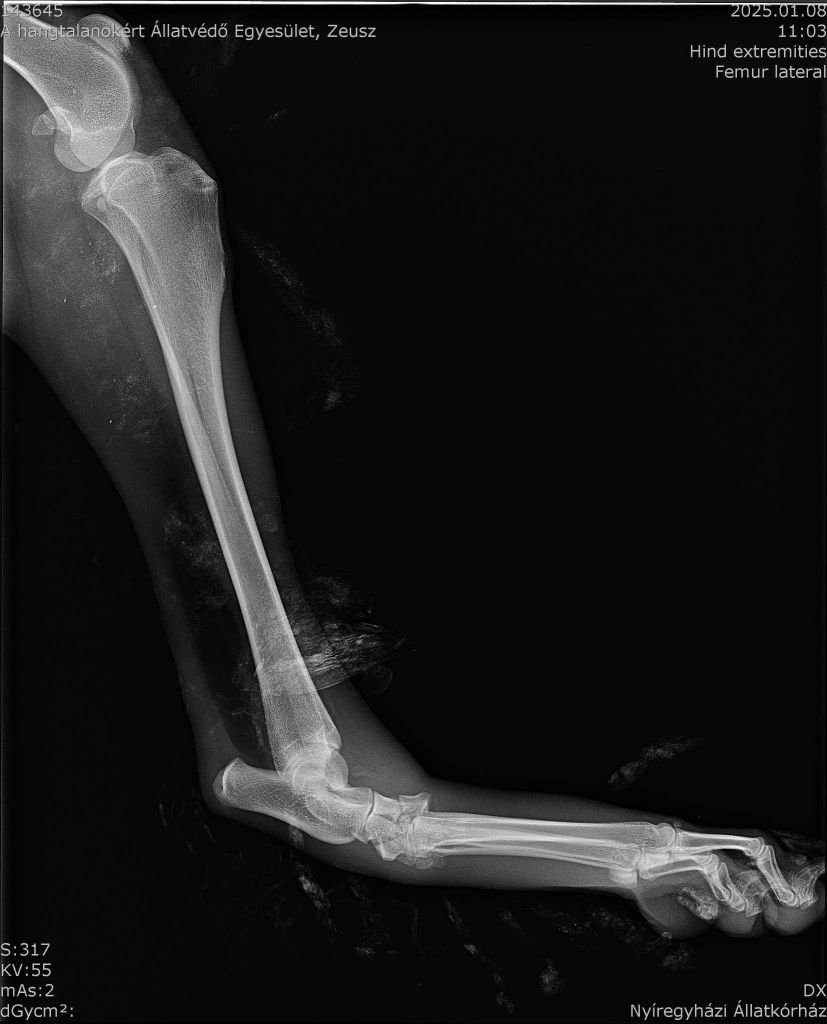

Das Röntgenbild hat verdeutlicht, dass Zeus nicht nur einen Bänderriss hat. Er hat ebenso eine Luxation im Fußgelenk. Das bedeutet seine Knochen haben ihre natürliche Ausrichtung verändert, wodurch Zeus Schmerzen im Sprunggelenk hat und nicht richtig laufen kann. Zeus wird daher diese Woche operiert, damit er bald wieder schmerzfrei laufen kann.